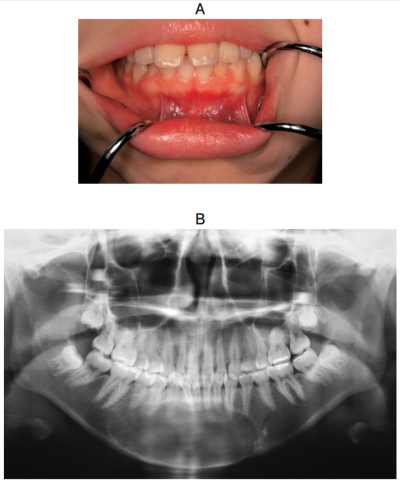

20歳の女性。下顎正中部の精査を希望して来院した。1週前に同部の無痛性のエックス線透過像を指摘されたという。5⏇5 には動揺はなく、歯髄電気診では生活反応があった。生検時には唇側の骨を含めて検体を採取した。初診時の口腔内写真、エックス線写真、CT、MRI T2強調像及び生検時のH-E染色病理組織像を別に示す。

診断名はどれか。1つ選べ。